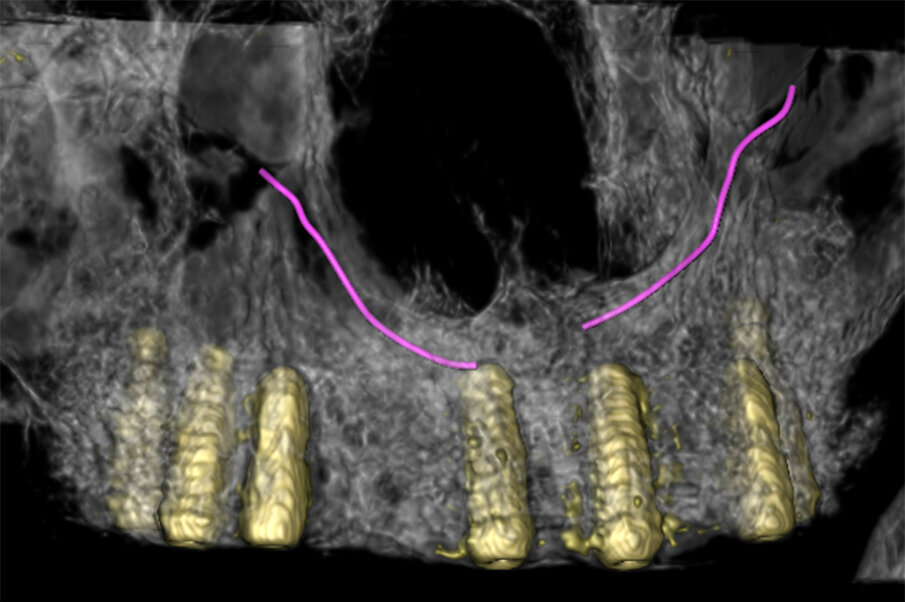

Fig. 1 - Decorso del CS simulato in un volume (rendering).

Fig. 7 - Volume rendering con CS in evidenza.